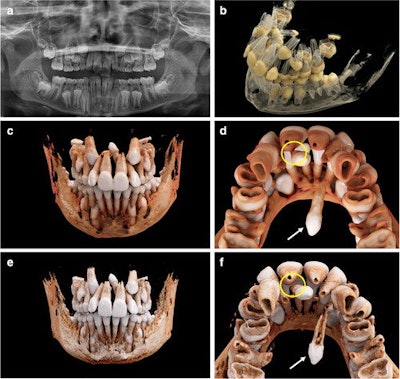

In the report, researchers used cinematic rendering for the volumetric image visualization of midface CT datasets. Predefined reconstruction parameters were specifically modified to visualize complex orthodontic cases in children with ectopic, impacted, and supernumerary teeth. Using the masking and windowing functionality of Siemens Healthineers' Cinematic Anatomy application, upper and lower jaw and respective dentitions were easily segmented, creating natural-appearing images for realistic representations of anatomy, the researchers stated.

"(Nevertheless,) the 3D spatial relationship of the teeth, as well as their structural relationship with the antagonizing dentition, could immediately be investigated and highlighted by separate, interactive 3D visualization after segmentation through windowing," Willershausen and colleagues wrote.